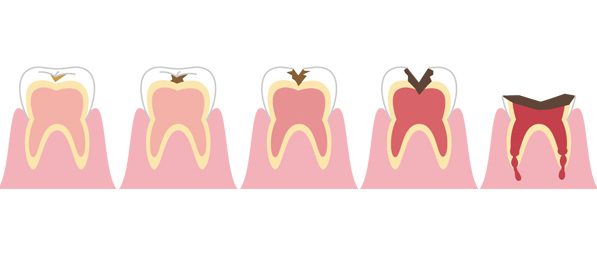

小さい虫歯の時はなるべく歯を削らない。虫歯が中等度に大きいときは神経を取りたくない。あまりに虫歯が大きい時は歯を抜きたくない。 今回は歯を抜きたくないに関係することを説明します。

虫歯が大きいと歯の内部の神経まで細菌が侵入し、神経を取らなくてはいけない、もしくはすでに神経が死んで腐敗している、以前にすでに神経を取っているということがあります。このような場合の治療は根管治療という方法で治していきます。

虫歯が進行する理由は細菌の繁殖です。

細菌が歯の内部に住み着いて、内部で増殖し、歯を溶かして、根の先の方まで進行し、骨まで溶かして膿を作ります。